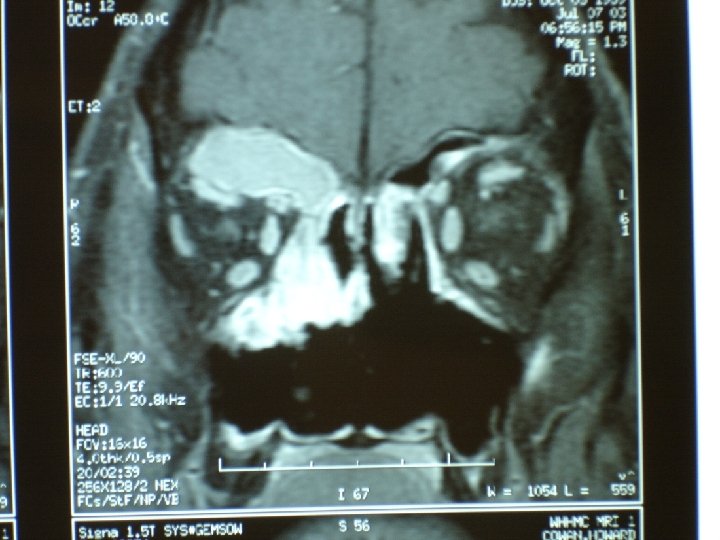

Chronic rhinosinusitis • Sinus CT scan • Consider anatomic factors— septal deviation, nasal polyps, concha bullosa, ostio-meatal blockage

Indications for sinus surgery • Nasal polyposis • Anatomic blockage—deviated septum, enlarged turbinate, concha bullosa • Mucocele • Orbital abscess

Indications for sinus surgery • Fungal sinusitis—allergic vs. invasive (mucor) • Tumor of nasal cavity or sinus